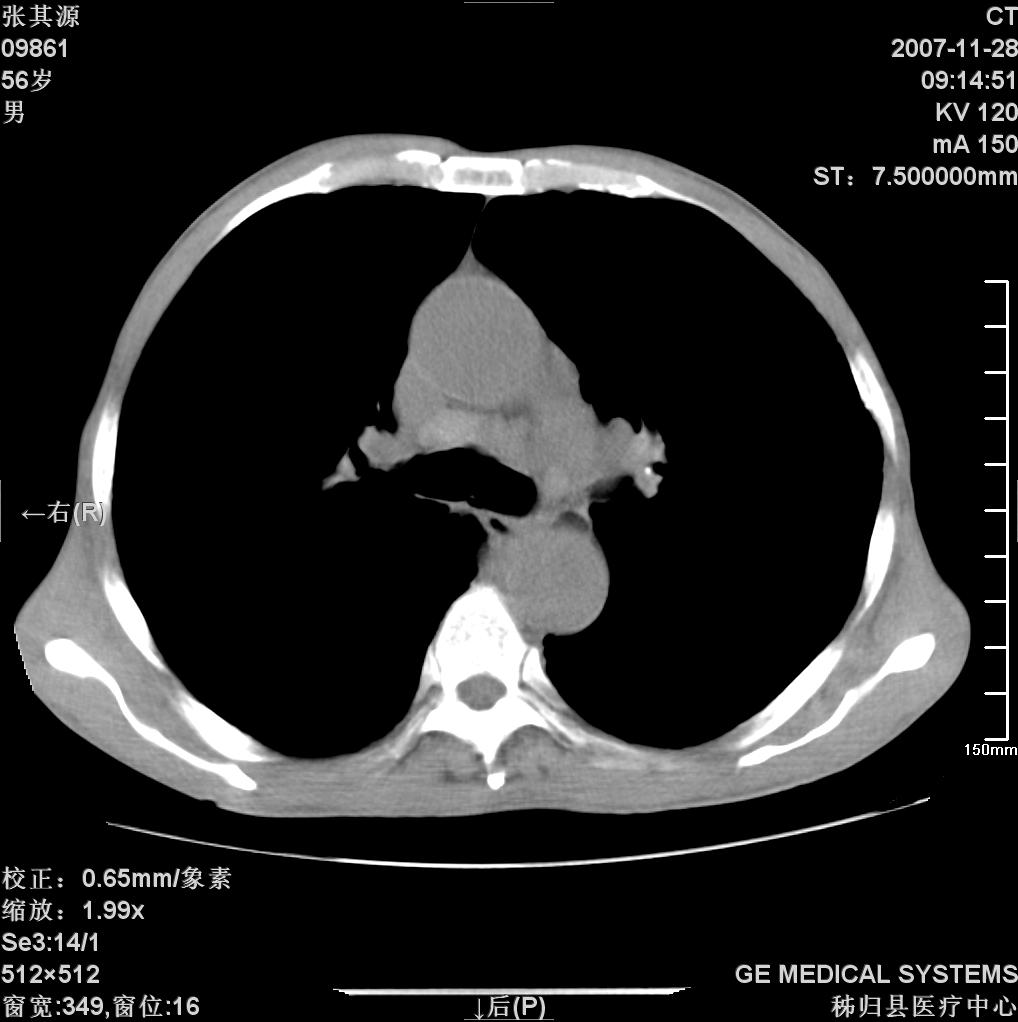

患者因阻塞性黄疸入院,发病前10天持续中等程度发烧.术前检查发现两肺弥漫性病变,请各位大虾会诊,除了考虑急性血源性肺结核外,还有其他什么疾病可能.

补充一下,该患者没有与尘肺相关职业史。请大家帮忙会诊一下,外科医生打算为其做胆总管肿瘤做手术的,现在在等我们的结果。谢谢各位了。

双肺多发粟粒样病灶,右肺胸膜下结节样病灶,气管前腔静脉后及隆突下均见肿大淋巴结,结合胆道肿瘤病史首先考虑转移。另外心影密度略低,时间格显示,是否有贫血?查明白再手术吧!